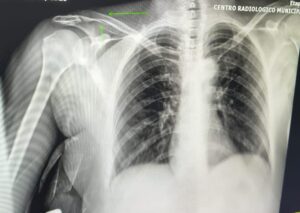

De acordo com boletim de ocorrência, D. G.S.N, de 29 anos, agrediu a mãe de 55 e o irmão dele de 21. De acordo com boletim de ocorrência registrado na Central de Polícia Judiciária, a Guarda Civil Municipal foi acionada para atender uma confusão entre familiares. Quando os guardas chegaram ao local, encontraram uma ambulância socorrendo a mulher de 55 anos. A mulher apresentava sangramento e graves lesões. Na casa também estava o agressor e o irmão de 21 anos. O rapaz de 21 anos estava muito abalado e contou, que ele e o irmão estavam brigando, a mãe teria tentado apartar a briga e teria sido violentamente agredida pelo filho de 29 anos. O rapaz de 21 anos disse que também havia sido agredido pelo irmão de 29. , D. G.S.N, teria usado um objeto contundente para agredir a mãe. O acusado admitiu ter agredido a mãe e também o irmão. Alegando, contudo, ter utilizado as próprias mãos e também um rodo. A vítima foi encaminhada ao hospital municipal de Ibaté, onde foi constatado quadro clínico grave, com fraturas na região do maxilar, clavícula e região occipital, permanecendo impossibilitada de prestar declarações. Devido à gravidade das lesões, a mulher foi transferida para a Santa Casa de São Carlos. A ocorrência foi apresentada na Central de Polícia Judiciária de São Carlos, onde o detido foi autuado em flagrante por lesão corporal e tentativa de homicídio e recolhido ao Centro de Triagem de São Carlos.

Foto das lesões da vítima.